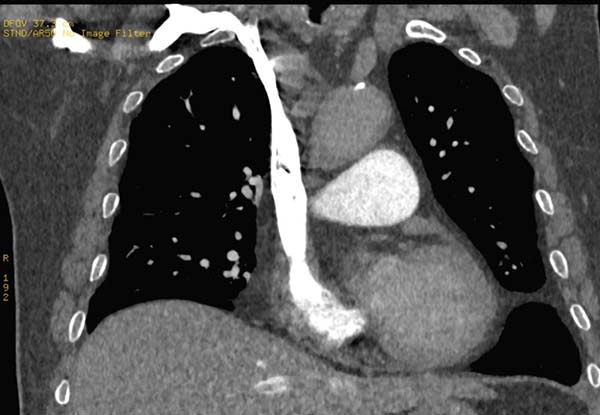

当对比剂到达锁骨下静脉、头臂静脉时,左右两侧的路径发生分歧,右锁骨下静脉→右头臂静脉路径距右心房的距离要明显短于左锁骨下静脉→左头臂静脉路径,右锁骨下静脉连接右头臂静脉后直接汇入右心房,而左锁骨下静脉连接左头臂静脉的同时需跨越左颈总动脉、头臂干,部分情况下还会受到主动脉弓的影响。

如下图所示

右锁骨下静脉经头臂静脉直接进入上腔静脉